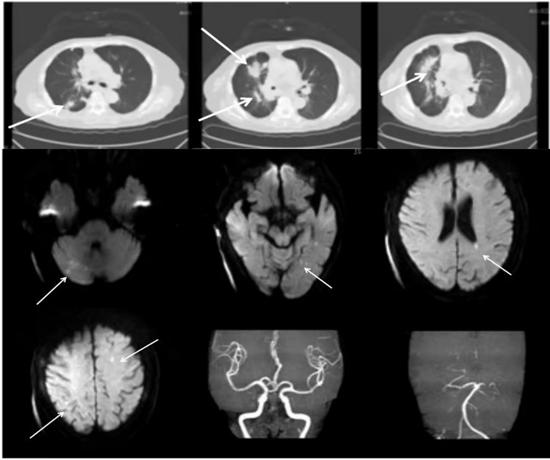

图14 胸部CT示右肺多发占位性病变;头部MRI示双侧额顶叶、左侧颞枕叶及右侧小脑多发脑梗死;MRA示左侧大脑后动脉P1远端重度狭窄或闭塞(图源 作者提供)头部核磁提示三流域(双侧前循环和后循环)均存在DWI高信号的急性多发小灶性脑梗死,病灶呈播散性而非单一动脉供血区,显然用左侧大脑后动脉狭窄不能解释。特鲁索综合征:恶性肿瘤病史+D二聚体升高+三个或三个以上血管供血区急性脑梗死+头颈部责任血管无明显狭窄。